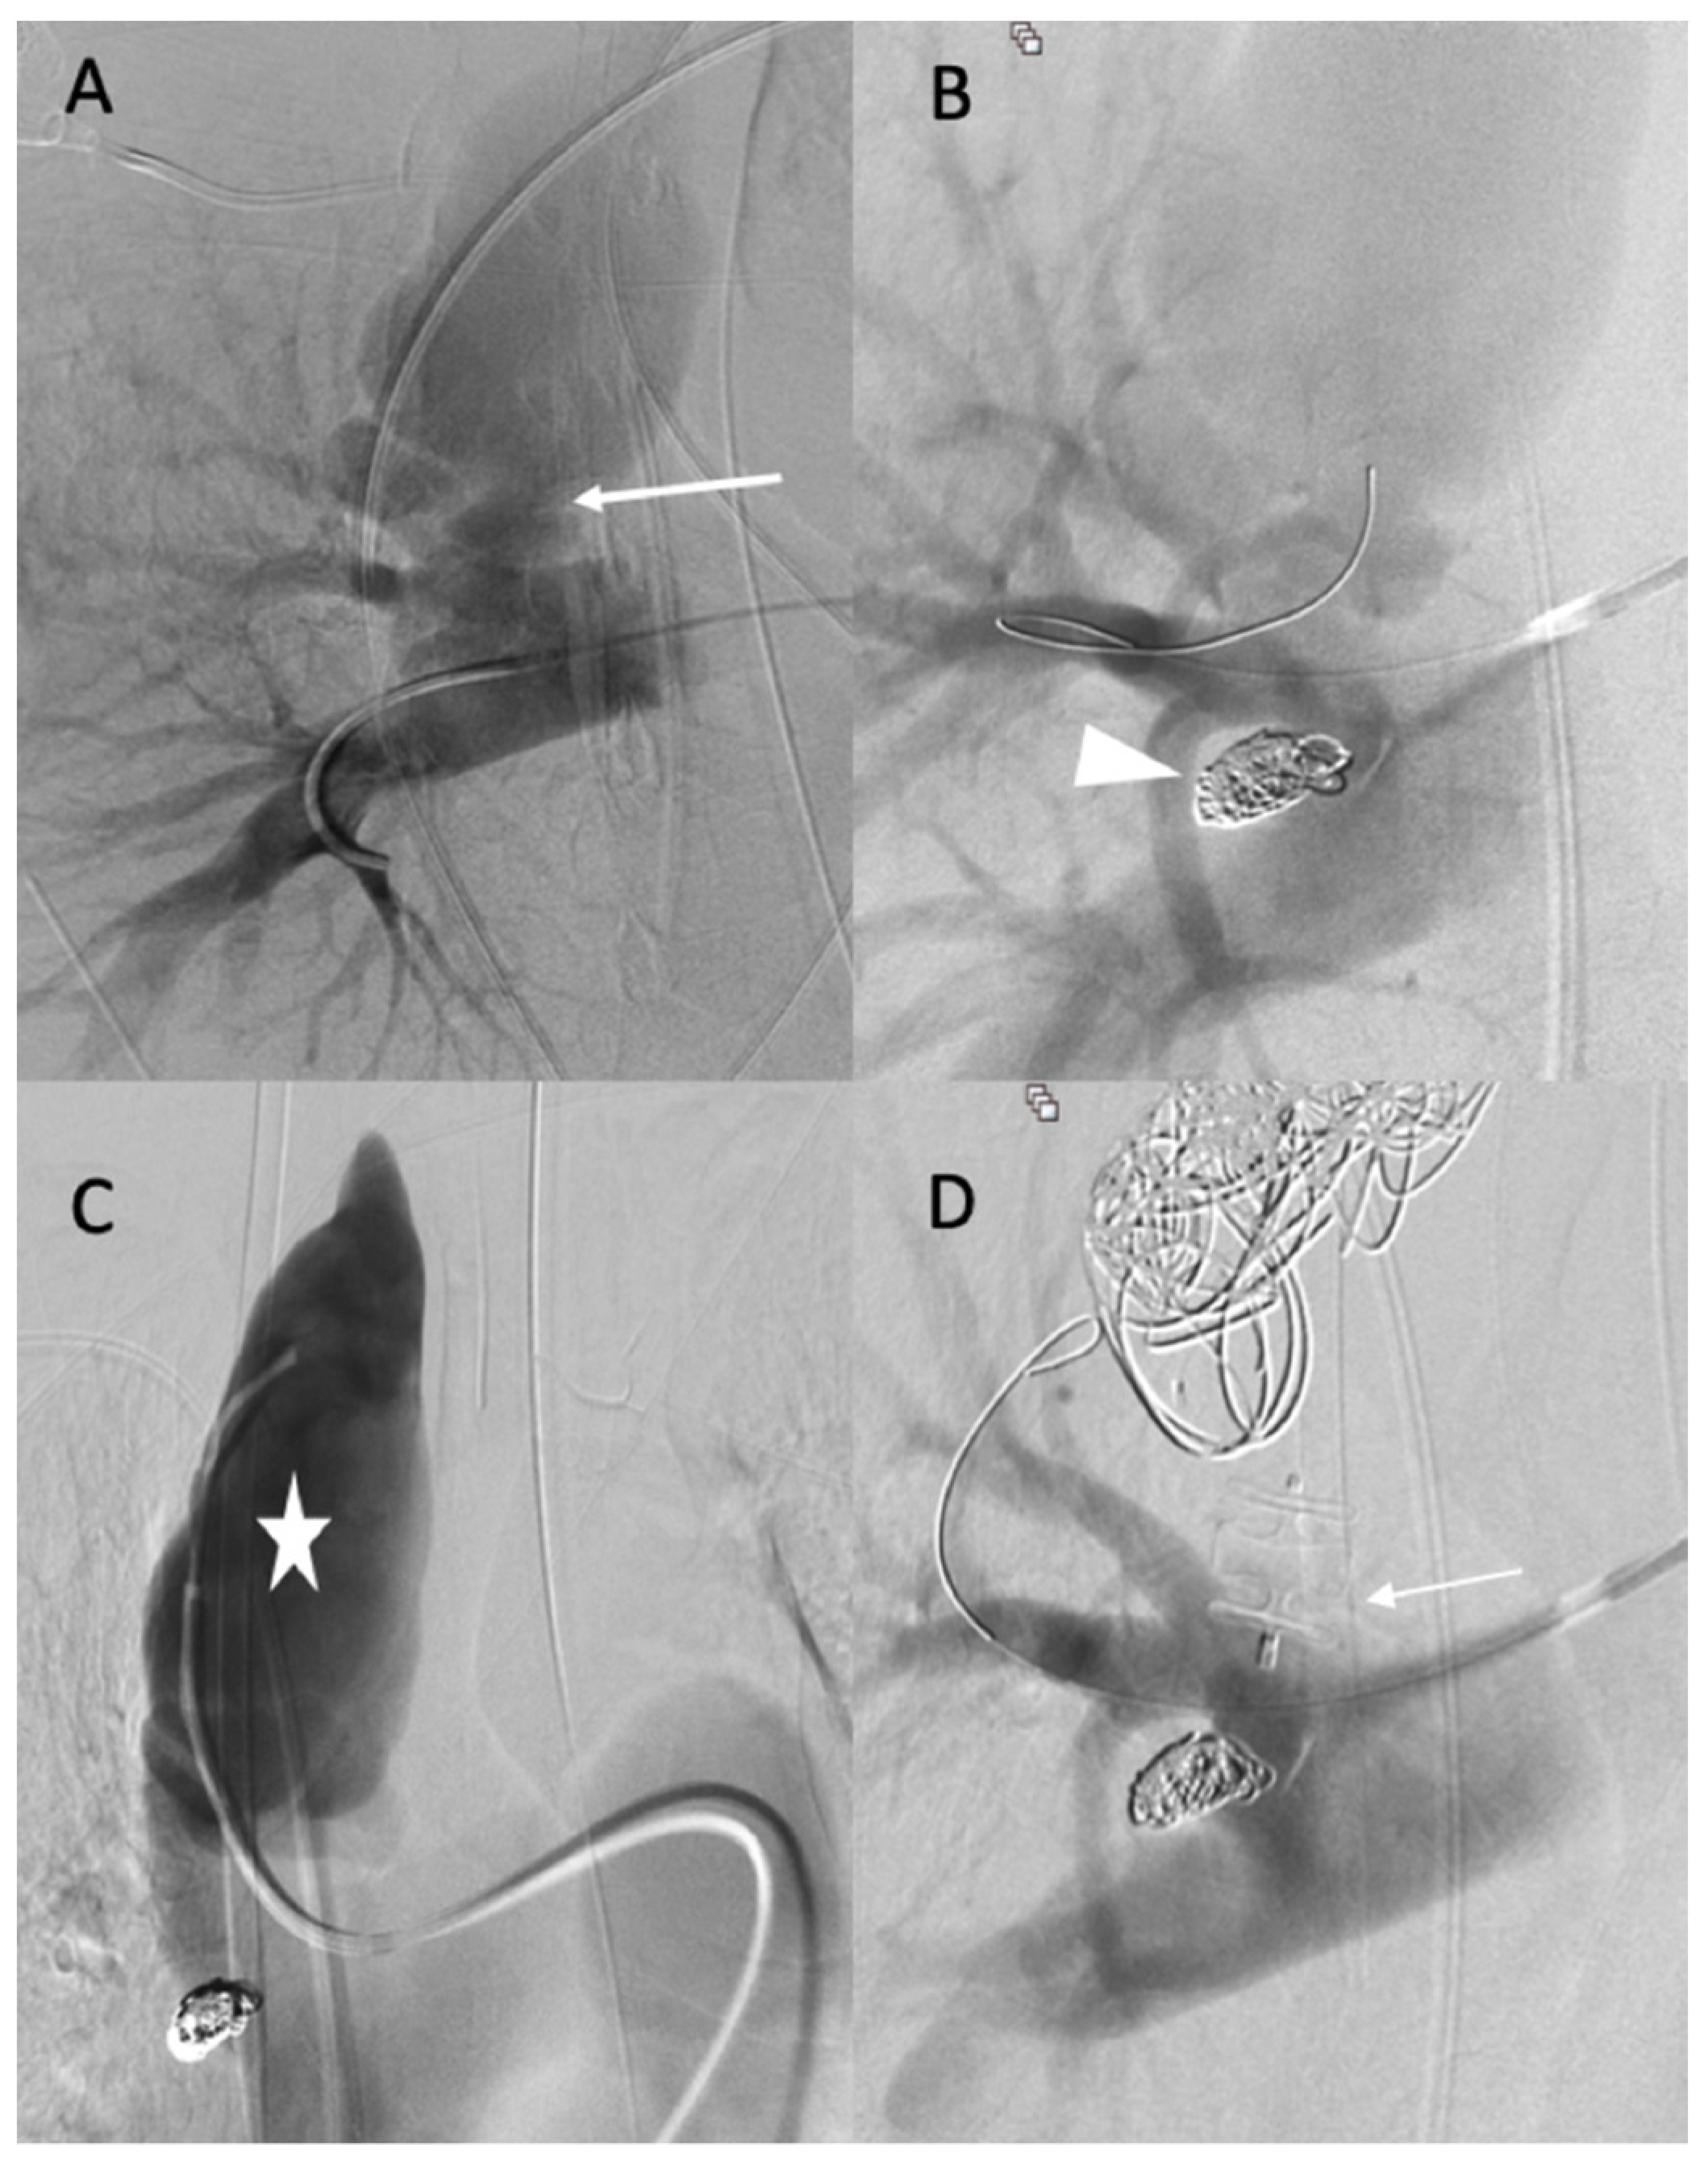

The diagnosis of EDS was suspected based on the patient’s clinical history and CT scan findings, and endovascular management was decided with a thoracic surgeon. Under local anesthesia, a 10 F introducer sheath (Radiofocus® introducer II, Terumo Corporation, Tokyo, Japan) was inserted via the right femoral vein. The right pulmonary artery was catheterized using a 6 F ENVOY catheter (Codman-USA), and the distal segment of the arteriovenous fistula was occluded using multiple 0.035 hydrocoils (Figure 2A,B). The ostium of the arteriovenous fistula was occluded with second-generation plugs (AMPLATZER-USA) (Figure 2C), and the pseudoaneurysm was occluded using multiple 3D coils (Figure 2D).

Figure 2.

(A,B) Before and after the occlusion of the distal portion of the arteriovenous fistula (arrow, head arrow). (C) Before the occlusion of pseudoaneurysm (star). (D) The occlusion of the proximal portion using first- and second-generation plugs (arrow), and the occlusion of the pseudoaneurysm using multiple 3D coils.